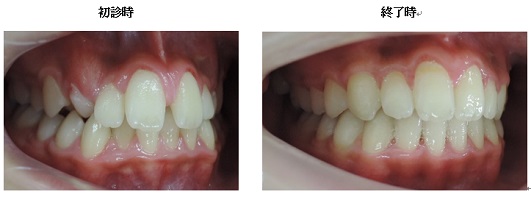

以下の上顎の症例では左右の第一小臼歯を抜かないと治療出来ないと説明があるはずです。しかし、当院での治療終了時には顎骨が拡大して綺麗に歯が並んでいます。

初診時 終了時

当院では拡大装置などを使用する事無く歯並びを綺麗に並べることが出来ます。

治療期間3年0か月で機能的で美しい咬み合わせが完成しました。

今回の症例は一般的に抜歯(第一小臼歯)が必要な症例ですが当院では非抜歯で治療する事が出来ました。